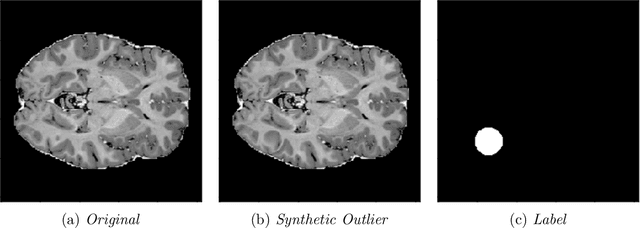

Abstract:We introduce a new self-supervised task, NSA, for training an end-to-end model for anomaly detection and localization using only normal data. NSA uses Poisson image editing to seamlessly blend scaled patches of various sizes from separate images. This creates a wide range of synthetic anomalies which are more similar to natural sub-image irregularities than previous data-augmentation strategies for self-supervised anomaly detection. We evaluate the proposed method using natural and medical images. Our experiments with the MVTec AD dataset show that a model trained to localize NSA anomalies generalizes well to detecting real-world a priori unknown types of manufacturing defects. Our method achieves an overall detection AUROC of 97.2 outperforming all previous methods that learn from scratch without pre-training datasets.